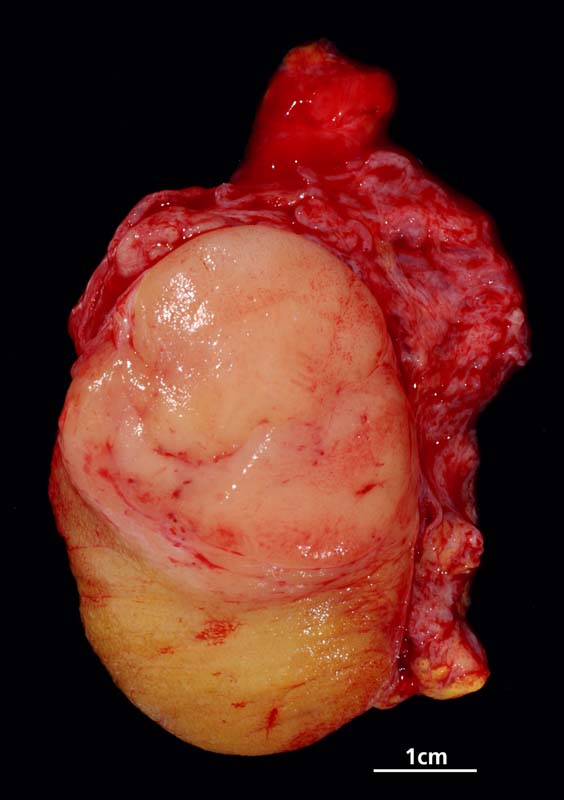

Makroskopisch imponieren Seminome als gut begrenzte weiche crèmefarbene Knoten oder diffuses Intiltrat. Mikroskopisch findet sich eine uniforme Population grosser Zellen mit prominentem zentralem Nukleolus, welche durch schmale Bindegewebssepten voneinander getrennte Nester bilden. Ein leukozytäres Entzündungsinfiltrat, synzytiotrophoblastäre Riesenzellen und Mikroverkalkungen können zusätzlich vorhanden sein. Gelegentlich induziert der Tumor eine ausgeprägte granulomatöse Entzündung. Dies kann zur Fehldiganose einer granulomatösen Orchitis führen.

• Scharf begrenzter Tumorknoten mit eosinophilen Nekrosearealen.

• Tumor nicht einschneiden (Beurteilung wird erschwert).

• Gewebe möglichst rasch und vorzugsweise frisch einsenden.